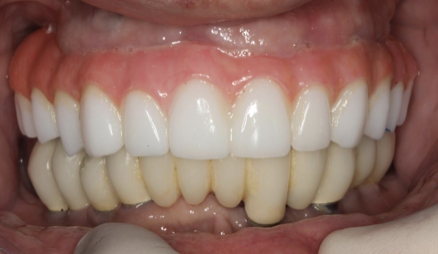

Patient Factors that May Contraindicate Fixed Implant-supported Prosthetics

(42.) Fixed-removable prosthesis.

Figure 42

(43.) Fixed-removable prosthesis.

Figure 43